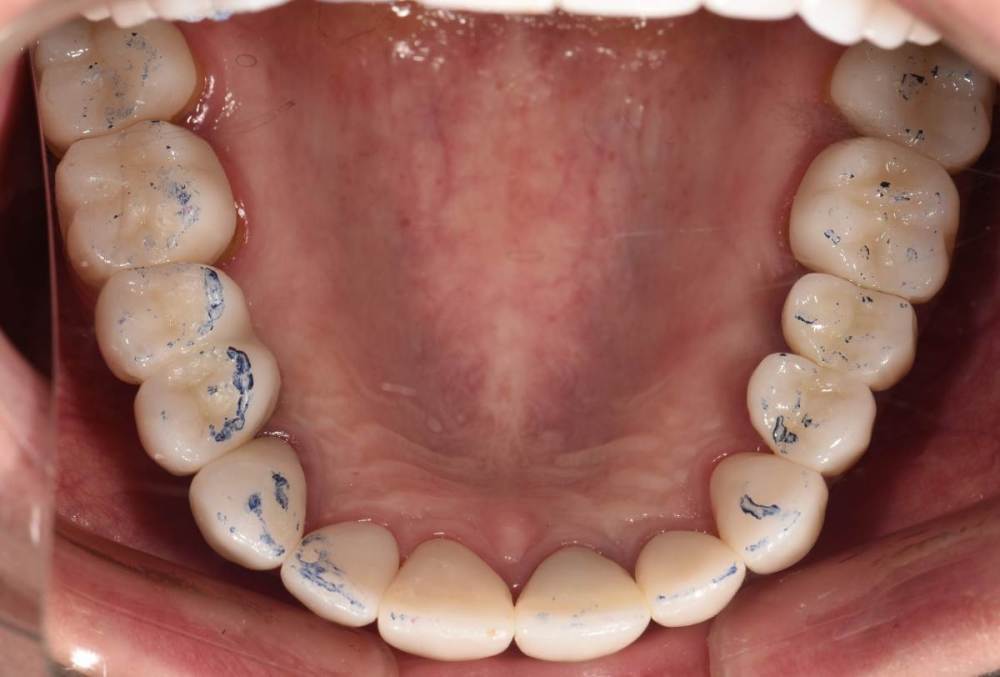

Финал работы:

DSC_3144.thumb.JPG.c9e60b8847f66dc01ba0e6e1113ab39b.JPGDSC_3145.thumb.JPG.1723748a079bc482f1a7e4534aff8f33.JPGDSC_3146.thumb.JPG.6dd4d0eb29dc3e6e92773c3c7892f692.JPGDSC_3147.thumb.JPG.e4f9cc2d841e3b7ff3aa73491ba9b4a3.JPGDSC_3148.thumb.JPG.0f174600adf2a49d65266a0ff665abfd.JPGDSC_3149.thumb.JPG.c9849be795d45b2573488d4545f3843f.JPGDSC_3150.thumb.JPG.6380366ecde7802fa32c6471b8b33883.JPGDSC_3153.thumb.JPG.1420d109d08ed1d6bd63447fe73eeed6.JPGDSC_3154.thumb.JPG.04b902149b3c0f9f2f1bcfa2e310c855.JPG

Фото спустя месяц после фиксации. Сначала нижняя челюсть, потом верхняя. Решение с передними нижними зубами - компромиссное. Все они витальные, имели 2-3 степень подвижности. После исправления положения нижней челюсти и установления правильных окклюзионных контактов - 1-2 степень подвижности. По поводу гигиены пытаемся.